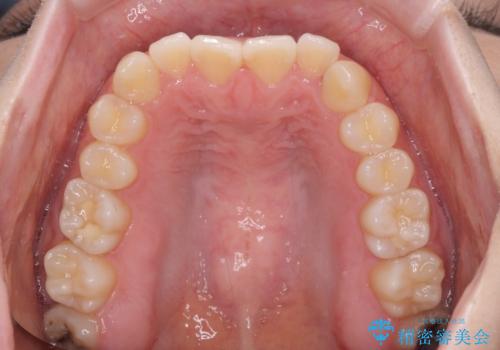

前歯のクロスバイト インビザラインによる矯正治療

- 前歯のクロスバイトとデコボコを気にして来院された患者様です。

骨格的に下顎前突傾向であるため、自己管理が煩わしくないようであれば、インビザラインによる矯正治療がお勧めとなります。

インビザラインを用い、下顎歯列を後方に移動させながら全市の被蓋を改善し、歯並びを整えていくこととしました。

途中マウスピースが使用できず、来院されない期間があり、治療期間は長くかかりましたが、無事に治療を終えることができました。